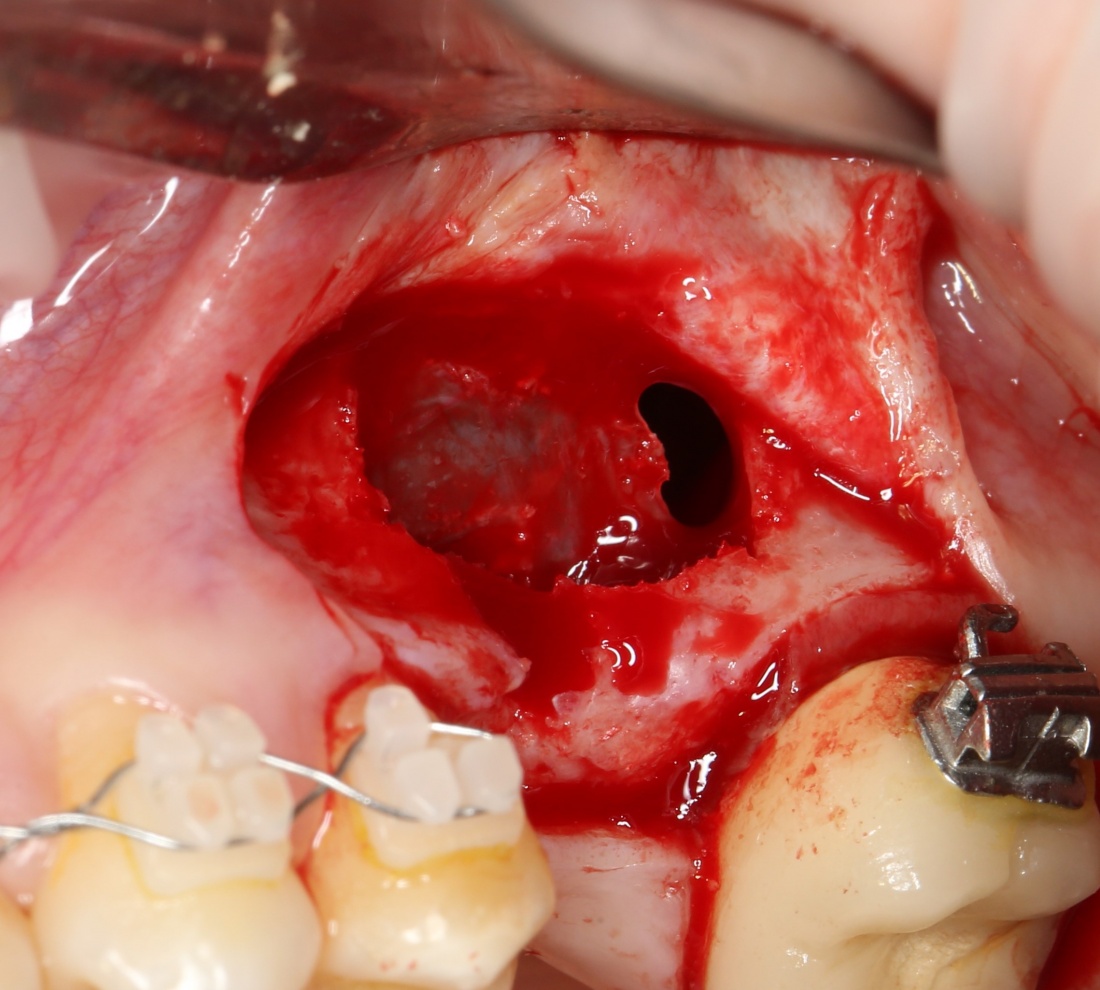

Синуслифтинг: что делать при перфорации слизистой оболочки гайморовой пазухи?